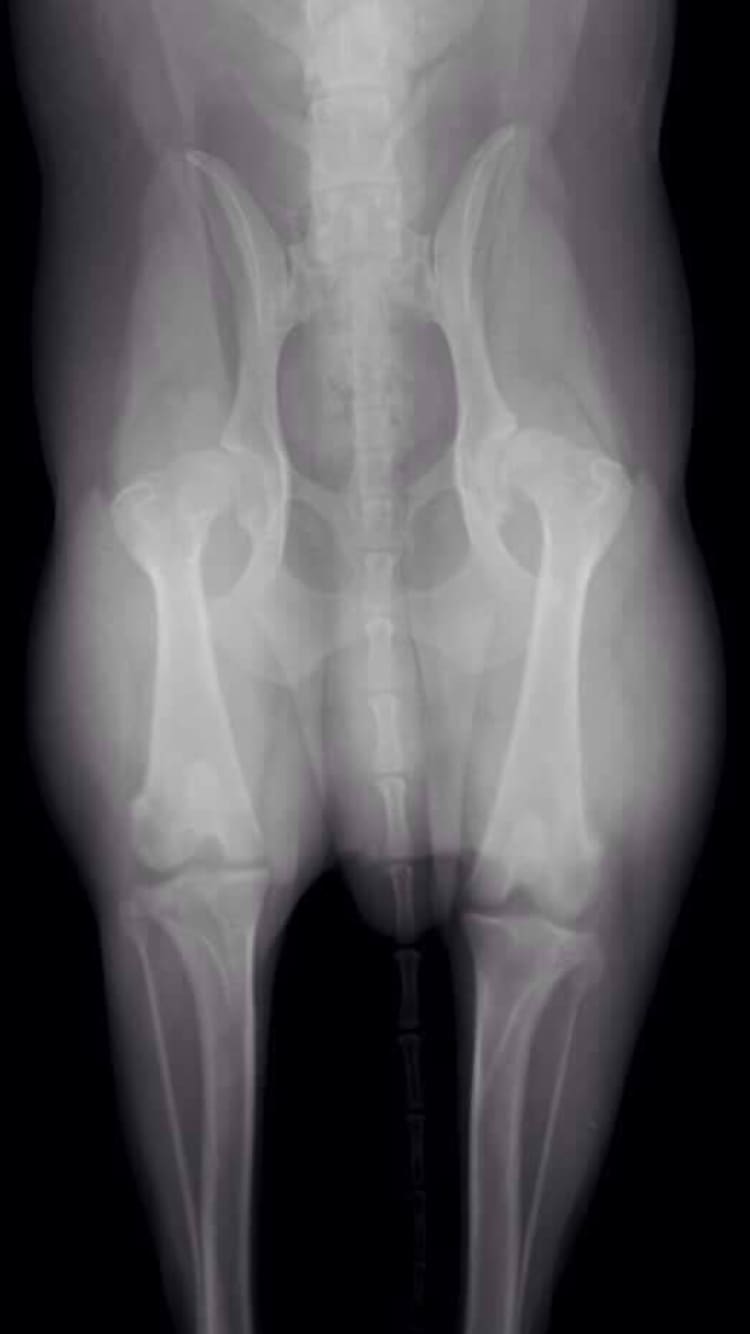

From the picture attached, can you tell if what grade or how severe the hip dysplasia is? My dog is not showing any pain other than limping after a nap. He just started on Glucosamine & Chondroitin. Thanks in advance

Legally, I am not allowed to give you a diagnosis, but based on the x-rays you posted, I suspect that your vet told you that Sly has significant hip dysplasia and arthritis in both hips. I'm sure that came as a surprise to you since Sly is only showing some limping after resting. Dogs are very stoic and do not show us pain as we would expect. Since you have just started Sly on a glucosamine and chondoitin sulfate supplement, you certainly could wait and see how he does on that, but I suspect you will need to add some additional supplements or medications to resolve his limping, so don't be afraid to talk to your vet about those. We frequently use fish oil, MSM, non-steroidal anti-inflammatory drugs, and many other drug combinations for arthritis. I also highly recommend physical rehabilitation and acupuncture. Although we expect our dogs to cry in pain, most dogs with arthritis pain act exactly like Sly and only limp after getting up. Our goal with treatment is to get them to the point that their pain is so well controlled that we don't notice them limp at all. I hope that helps! Thanks for using Petco Pet Education Center, formerly Petcoach.